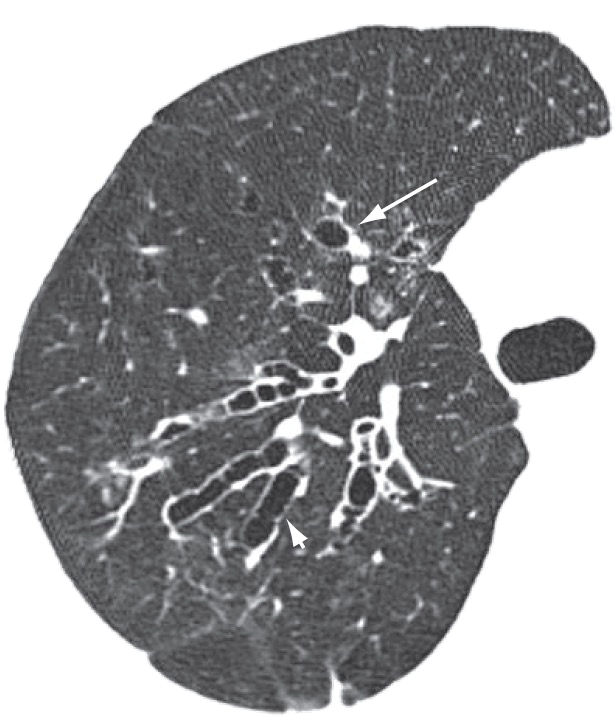

在正常情况下,支气管分支与肺动脉或支气管动脉相伴,支气管分支的直径与毗邻肺动脉或支气管动脉的直径相等。而在支气管扩张症患者的胸部CT(尤其是HRCT或MSCT)中,由于扩张的支气管分支直径超过肺动脉或支气管动脉直径(一般超过1.5倍),因此支气管扩张症在轴位图像上形成与印戒相似的常见征象(即印戒征),如下图所示。

左图:支气管扩张症患者的胸部CT:左肺下叶可见扩张的支气管与邻近肺动脉形成印戒征(箭头)。右图:印戒[2]

印戒征可见于肺野中的任何部位,但更常见于中等大小的支气管[1-2]。在一项针对支气管扩张症患者的胸部MSCT扫描的回顾性研究中,支气管扩张症的影像学征象中以印戒征最为常见(35.9%)[3]。

支气管扩张症:印戒征(长箭头)和双轨征(短箭头)[4]